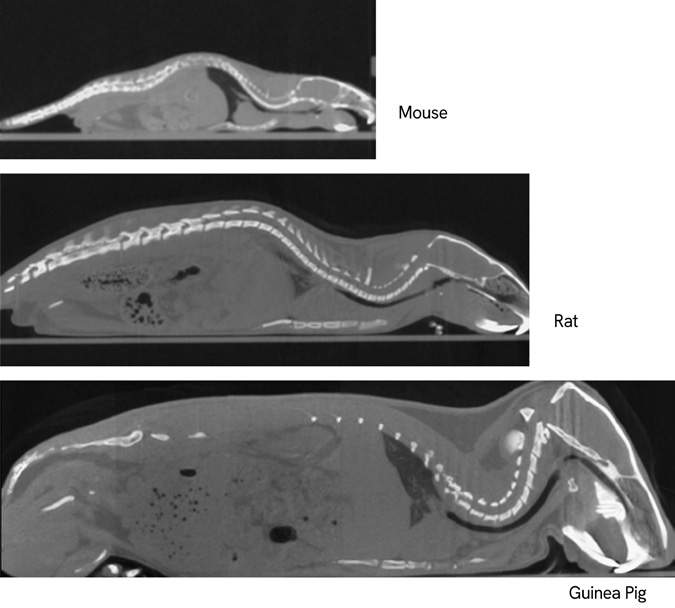

GX IIIは、マウスから小型ウサギまでのさまざまな種のin vivoイメージングだけでなく、より高解像度なex vivo イメージングも可能となり、さまざまなサンプルをより最適な測定方法で撮影できる幅広い柔軟性を提供します。

- 5種のFOV:8mm, 18mm, 36mm, 72mm, 86mm

FOV(視野)とサンプル種の例

| FOV | サンプルや対象物の例 |

|---|---|

| 8mm | Ex vivoサンプル |

| 18mm | ゼブラフィッシュやその他の小さなサンプル |

| 36mm | 標準的なマウスイメージング |

| 72mm | ラットやウサギ |

| 86mm | 大型動物の肺を1回のスキャンで撮影 |